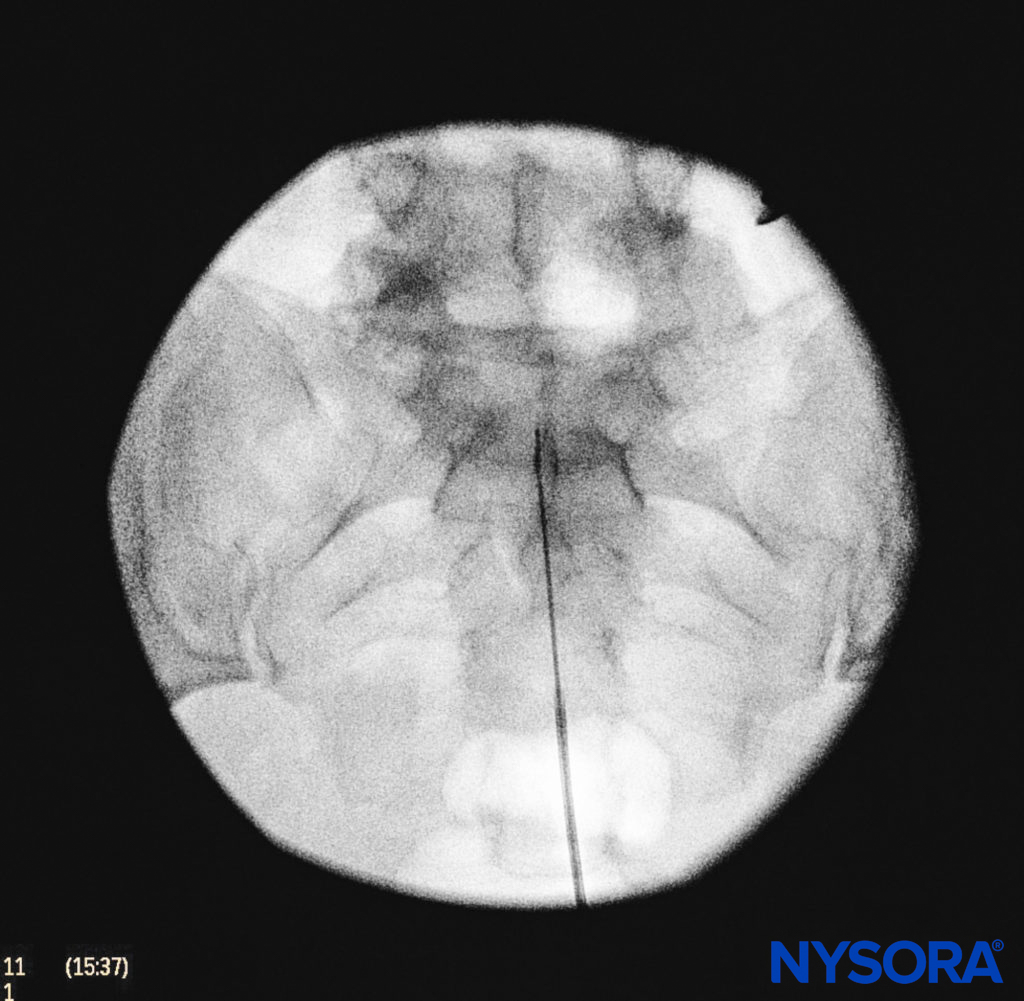

We utilize the anteroposterior view once the epidural needle is safely situated within the canal, and the epidural catheter is advanced cephalad (Figure 7, Figure 8). In this projection, the intermediate sacral crests appear as opaque vertical lines on either side of the midline. The sacral foramina are visualized as translucent and nearly circular areas lateral to the intermediate sacral crests. The presence of intestinal gas may obscure the recognition of these structures. A syringe loaded with either air or saline containing a small air bubble is then attached to the needle, and the loss-of-resistance technique is used to establish entry into the epidural space.

FIGURE 8. Anteroposterior fluoroscopic imaging depicting proper placement of the needle.

FIGURE 9. Anteroposterior fluoroscopic image depicting the catheter advanced to the L5–S1 interspace.